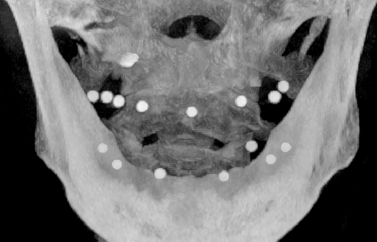

• CBCT第一次扫描(病人戴着放射导板)

• CBCT第二次扫描(单独扫描的放射导板影像)

安插多个放射阻射点(放射导板基托必须保证没有金属)

放入阻射物

• 阻射物必须突出基托表面0.5-1mm,去除干净周边粘接剂

• 用球钻在基托表面定位时,切勿穿透至组织面,切勿破坏组织面完整性

咬合稳定、就位准确、进行CT拍摄

第一次CBCT数据要求 :

• 患者戴着放射义齿拍摄,放射导板在口内与黏膜完全贴合密闭

• 除放射标记点外不得有任何金属物或阻射物

• 使用非阻射材料取咬合记录

• 保证咬合完全正确且稳定,无撬动及支点

单独扫描放射导板过程